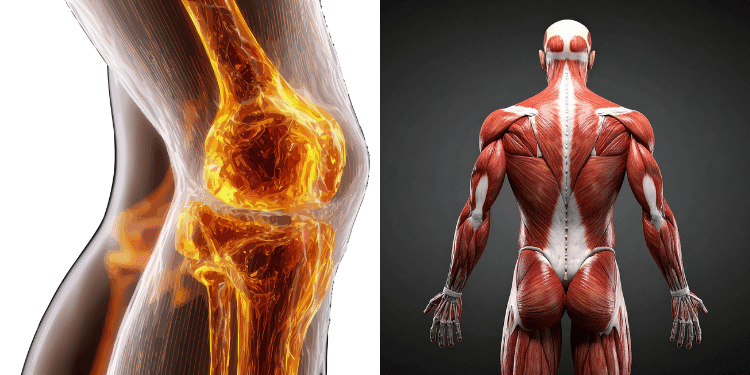

How Low Vitamin D Leads to Bone Discomfort

Bones are constantly renewing themselves. They are not static structures; they depend on a steady supply of nutrients to stay strong.

When vitamin D levels are insufficient, calcium absorption decreases. Over time, this can lead to bones becoming less dense and more sensitive.

This sensitivity is often felt as:

- A deep ache rather than sharp pain

- Discomfort in weight-bearing areas like legs and hips

- Increased tenderness when pressure is applied

The body is not necessarily injured – it’s simply not being supported at the level it needs.

Why Your Legs Are Often the First Place You Feel It

The legs carry most of your body weight, which makes them one of the first areas where imbalance becomes noticeable.

When bones are slightly weakened or muscles are not functioning optimally, the legs absorb the impact.

At the same time, vitamin D affects muscle performance. Low levels may lead to:

- Reduced muscle strength

- Faster fatigue

- A feeling of instability or heaviness

This combination – bone sensitivity and muscle weakness – creates that familiar aching sensation many people struggle with.